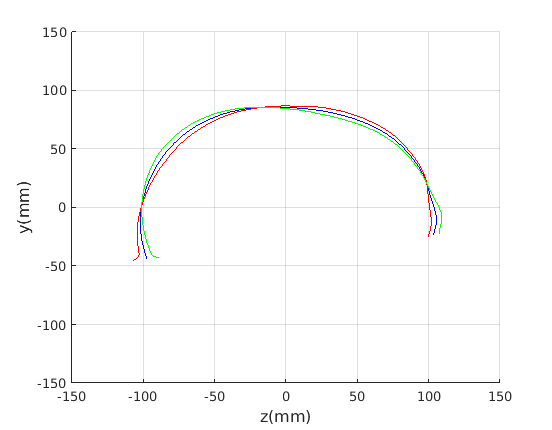

To emphasise the form/shape variation for each of these cases, the mean shape and shapes at mean for the four most significant modes of shape variation are plotted in Fig. 19 and Fig. 20. In this case, ECN normalisation is used.

For the cranial sagittal profile model, when not scale-normalised (Fig. 20, left column), the following dominant shape modes are observed:

-

1.

Cranial height variation with a low correlation with cranial length.

-

2.

Cranial length variation with a low correlation with cranial height.

-

3.

A cranial bulge that varies between the front and rear of the cranium.

-

4.

This mode picks up minor variations on cranial shape and some noise where hair exits from the latex cap.

When data is scale normalised (Fig. 20, right column), cranial height and length are more significantly correlated, as shown in the first mode (top right in figure). The second mode model a bulge that can vary from the front to the rear of the cranium. Taken together, these two modes capture close to 90% of the variation in the training set. A two-dimensional model, based on these two modes is used in a clinical case study in Sect. 8.

To provide a comparsion with ECN, the form/shape variation modes extracted from a GPA-based alignment are given in Fig. 21 for full head and Fig. 21 for cranium only.